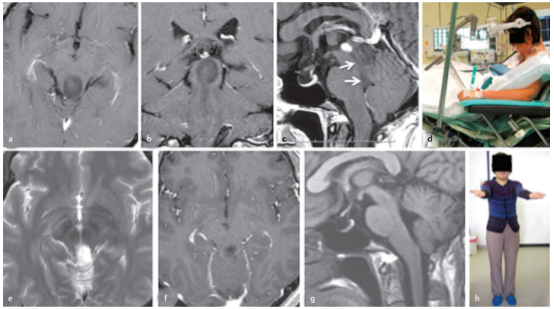

简要病史:36岁的女性因一个外生型顶盖肿瘤引起的闭塞性脑积水而出现严重头痛和步态共济失调。在另一家医院进行脑室腹腔分流术后症状消失。

术前:轴位(a)、冠状位(b)和矢状位(c)T1加权增强MRI显示肿瘤的确切位置及其尾端延伸至四脑室(c,箭头所示)。

术中:(d) 半坐位手术。肿瘤上半部分经幕下小脑上入路切除,其余下半部分经四脑室经前额叶暴露切除。组织病理学诊断为乳头状胶质神经元瘤。

术后:术后轴位(e)、冠状位(f)和矢状位(g)MRI显示肿瘤全切除。较后一次核磁共振是在手术后11年进行的;(h) 病人没有任何症状,过着独自的生活。

A 36-year-old woman had severe headache and gait ataxia due to occlusive hydrocephalus, which was caused by an exophytic tectal tumor. The symptoms disappeared after placement of a ventriculoperitoneal shunt in another hospital. Axial (a), coronal (b), and sagittal (c) T1-weighted contrast-enhanced magnetic resonance images (MRIs) demonstrate the exact tumor location and its caudal extension into the fourth ventricle (c, arrows). (d) The patient underwent surgery in the semisitting position. The superior tumor portion was resected via the supracerebellar infratentorial route, and the remaining inferior part via the telovelar exposure through the fourth ventricle in the same surgical procedure. Histopathologically, a papillary glioneuronal tumor was diagnosed. Postoperative axial (e), coronal (f), and sagittal (g) MRIs documented total tumor removal. The last MRI was performed 11 years after the surgical procedure. (h) The patient remained symptomfree and was leading an independent life.